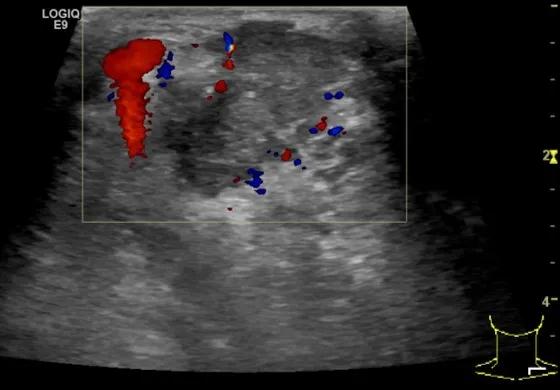

第5例是乳腺癌的患者,右乳恶性肿瘤术后化疗后1年出现淋巴结转移,患者基本情况差,拒绝放化疗,行局部热消融后也实现充盈缺损,术后一个月强化信号消失。

(病例5图例)